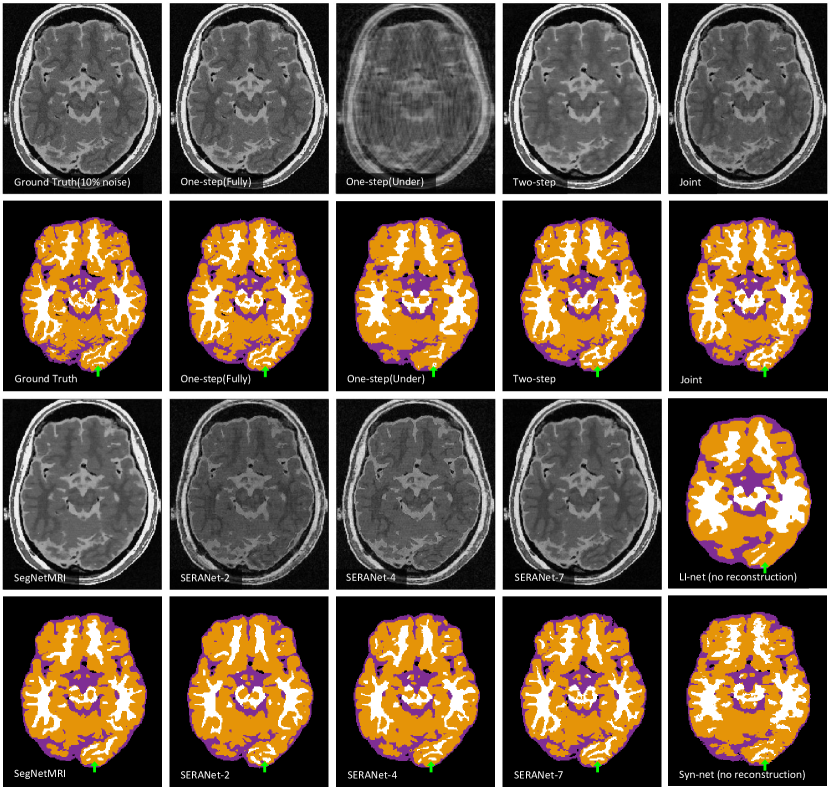

For visualization, we also train an One-step model that takes input as zero-filling images (inverse Fourier transform of under-sampled -space data) and outputs the segmentation maps. We visualize segmentation results and reconstructed images of models trained by 20% noise data in Figure 3. Our method SERANet predicts more accurate anatomical segmentation details and clearer image contrasts compared to Two-step and Joint. This shows SERANet overcomes the interference with noisy input by using the attention module.

We provide qualitative and quantitative comparisons to three state-of-the-art algorithms: LI-net[10] Syn-net[10], and SegNetMRI[11]. We also compare to the One-step model. We list the performance of SERANet-7 that with 7 reconstruction blocks and SERANet-2 that with 2 reconstruction blocks. The results of all methods are reported in Table 2. We also list whether the method is pretrained and what loss the method uses to optimize in column 2 and 3, respectively. For LI-net and Syn-net, since they perform segmentation from fully-sampled data as a warm start, we consider this as a pretraining technique. We observe that SERANet-2 and SERANet-7 consistently outperform the three state-of-the-art approaches for both 10% and 20% noises. Additionally, the Diceβs scores drop more for the SegNetMRI when noise level increases compared to SERANet, which may be due to the fact that SegNetMRI contains information from the noisy ground truth images. Example segmentation results are shown in Figure 4. Improvements of SERANet-7 on detailed anatomy structure are highlighted by the green arrows.

In this section, we provide additional quantitative results. We demonstrate the comparison results of our SERANet and other approaches on data with (Figure 8) white Gaussian noise and data with noise (Figure 9). For LI-net and Syn-net, we only show their segmentation results since they bypassed the reconstruction step. For our SERANet, we present the results of SERANet-2, SERANet-4 and SERANet-7 here.